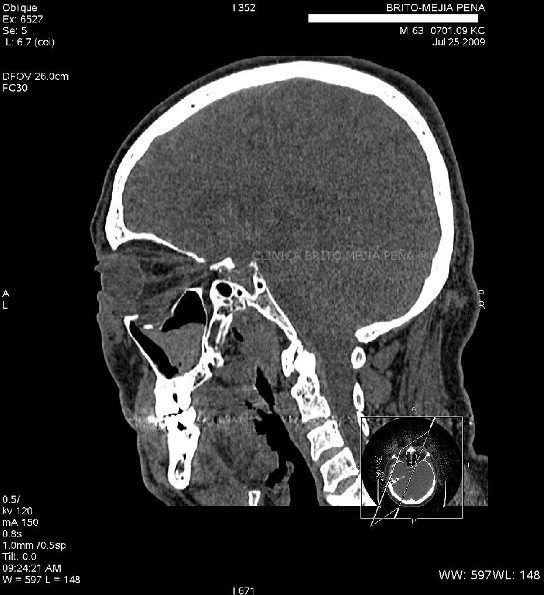

Fístula LCR sagital

Post Image